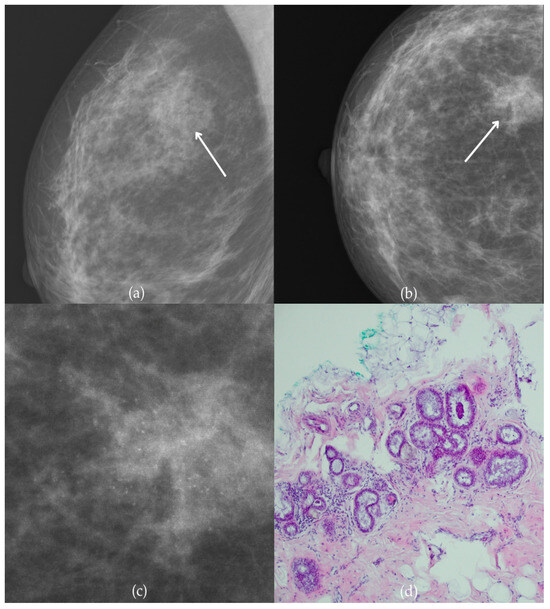

In Figure 2, mammographic and histopathological images illustrate the findings in a 51-year-old patient. The mammogram of the patient’s left breast shows architectural distortion with associated grouped amorphous calcifications over the 1 cm area in the upper outer quadrant, corresponding to a BI-RADS 4 finding. Tissue analysis obtained through biopsy confirmed morphological aspects of the DCIS (category B5a). Two years after the initial diagnosis, the most recent US follow-up was classified as BI-RADS 2, confirming benign findings.

Figure 2.

Ductal carcinoma in situ (DCIS). (a) Mediolateral oblique (MLO) view; (b) craniocaudal (CC) view of the left breast showing architectural distortion with associated grouped amorphous calcifications (marked with arrows) in the upper outer quadrant. (c) Magnified mammographic image of grouped amorphous calcifications within architectural distortion. (d) The histopathological image of the biopsy sample shows the characteristic features of DCIS with calcifications (marked with arrows) (HE staining; 100× magnification).